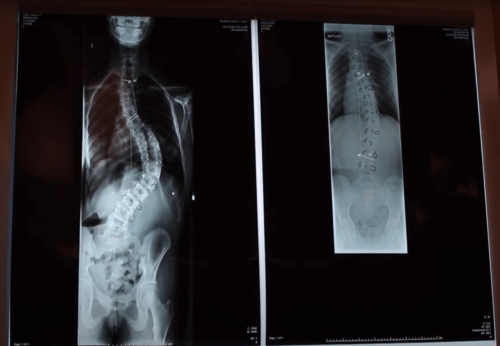

Alyssa Ebert: Before scoliosis surgery

Dr. David Schwartz performed scoliosis surgery on Alyssa Ebert.